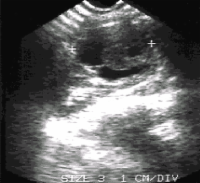

Am Beginn der Diagnostik steht die Sonographie (Abbildung 6). Neben dem Tumornachweis und der Zugehörigkeit zur Niere ist der Nachweis einer eventuellen Tumorinvasion in die Nierenvene (u.U. im Rahmen einer farbkodierten Dopplersonographie) bzw. in die Vena Cava inferior von Interesse. Immerhin bricht der Tumor in 11% in die Nierenvene und zu 6% in die Vena Cava ein, selten bis in das rechte Atrium (s. auch Abbildung 1c)

Der Wert der FKDS (farbkodierte Dopplersonographie= Angiodynographie = Farbdoppler) bzw. der kontrastverstärkten Sonographie ist zur Zeit noch nicht hinreichend belegt. Eine Verbesserung der Ergebnisse, auch hinsichtlich der Beurteilung der Nierenvene (z.B. Tumoreinbruch) ist zu erwarten